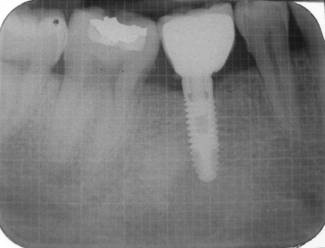

IOPA at the end of study period after 72 months

- IOPA at the end of study period after 72 months